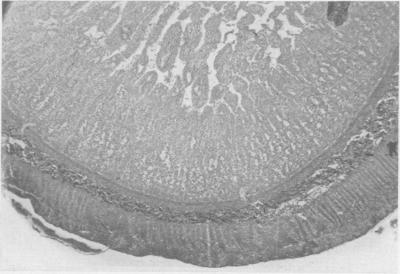

MEDINS G, LAUFMAN H

Ann Surg. 1958 Nov;148(5):747-54. doi: 10.1097/00000658-195811000-00004.